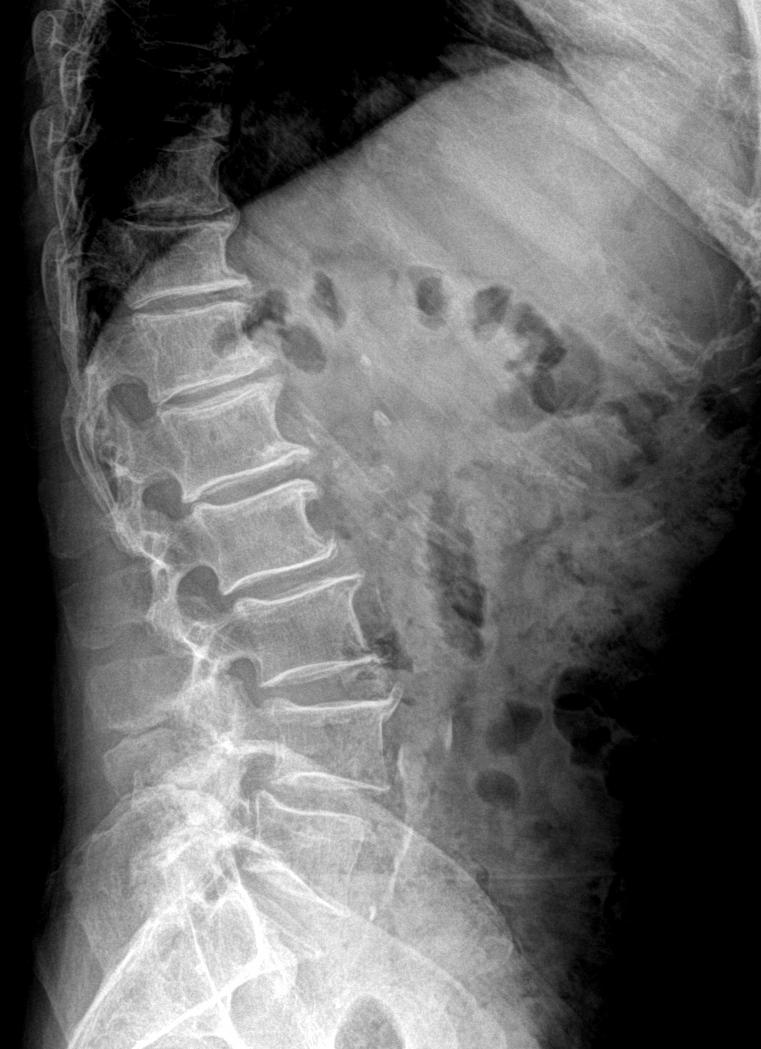

腰椎疼痛,滑脱几度?